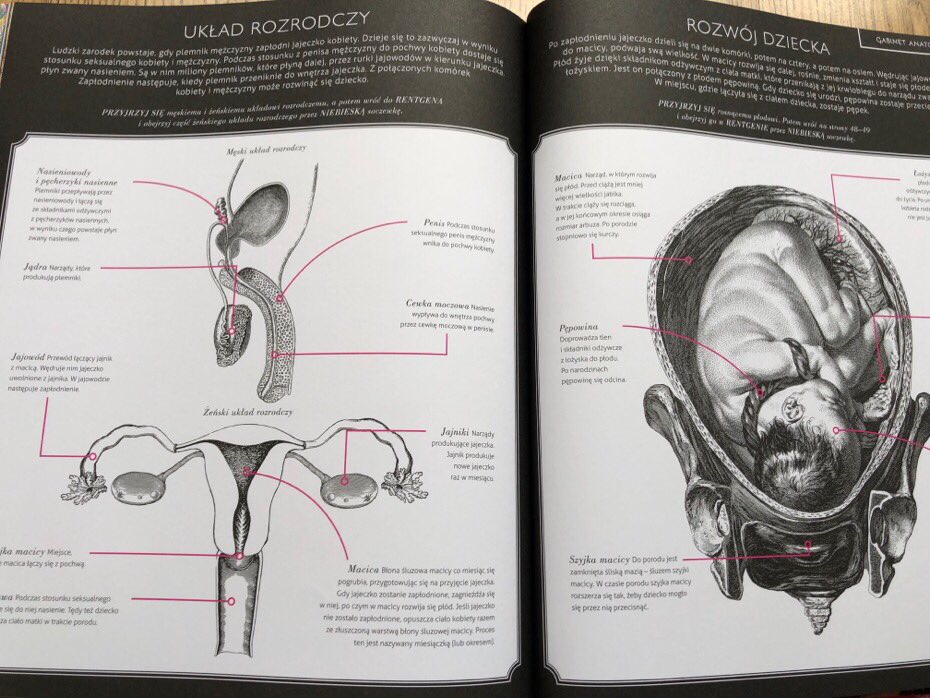

pokazanie danej części ciała (z podstawowymi informacjami na jej temat), rentgen i gabinet anatomii. Czytelnicy, za pomocą soczewek do przeglądania obrazów, mogą przestudiować kolorowe obrazy. Natomiast w gabinecie anatomicznym znajduje się dwustronicowy rozkład czarno-białych diagramów, który zawiera więcej informacji na każdy temat.

W jednej części książki opisano, jak rośnie dziecko, w tym podano informacje o narządach rozrodczych, wraz ze schematem organów wewnętrznych bez obrysu ciała. W tym temacie, gdy czytelnicy używają kolorowych soczewek w rentgenie, mogą zobaczyć szkielet, mięśnie brzucha i dziecko. Adaś zafascynował się płodem i z tego tytułu miał wiele pytań. Długo analizował rozwój dziecka i jego ułożenie.